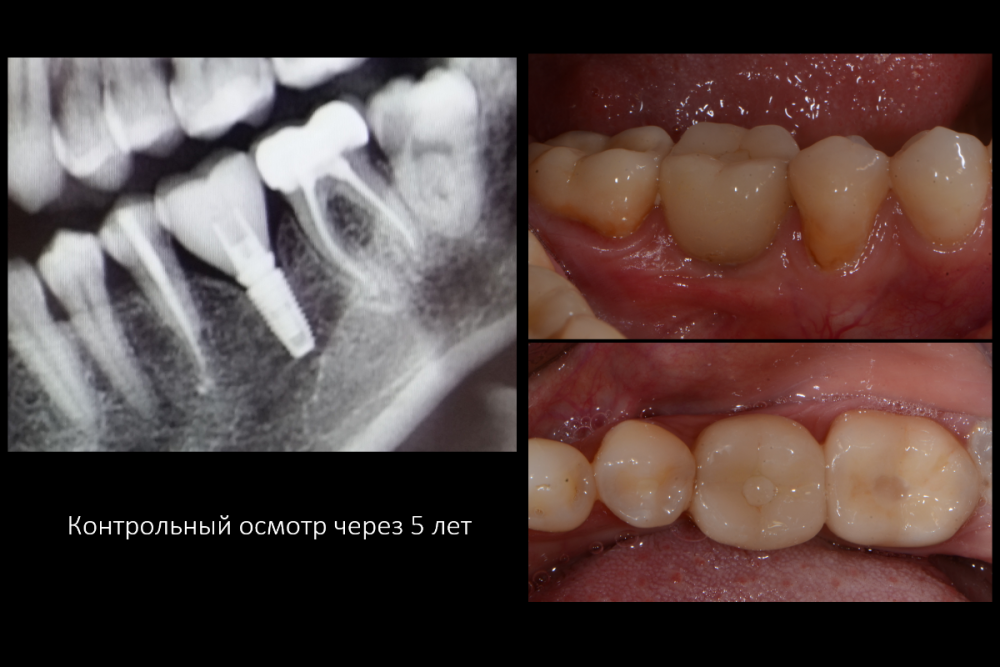

Карен Аванесов Опубликовано 28 июля, 2021 Поделиться Опубликовано 28 июля, 2021 В данной ситуации, просто, без мобилизации лоскута, за 15 минут, с учетом ожидания анестезии, установил имплантат, со своим фирменным заглублением , с хорошим торком, формирователь сразу, т.е. ничего особенного. Через 1.5 месяца можно протезировать, но вот незадача! Пациент удивляется, что-то быстро как то все прошло и операция и приживление, подозрительно... Давайте-ка повременим с постоянной коронкой, а то вдруг мало ли что там... Хорошо, делаем временную, на 3-6 месяцев. Прошло 5 лет, неожиданный комбек (причина хорошо видна на снимке).. Периодически приходится сталкиваться с такими недоверчивыми пациентами. Кейсом разумеется хватаюсь, но тут технику надо отдать должное, он молодец, у обычных растяп, через пару месяцев коронки и ломаются и пахнут, это с одной стороны хорошо, а с другой, еще лучше))) Я так понял, что кейсы где боль, кровь, стоны, отеки, в открытом доступе показывать не желательно, посему все культурно, без страданий, действительно, зачем стращать пациентов. 5 1 3 Ссылка на комментарий